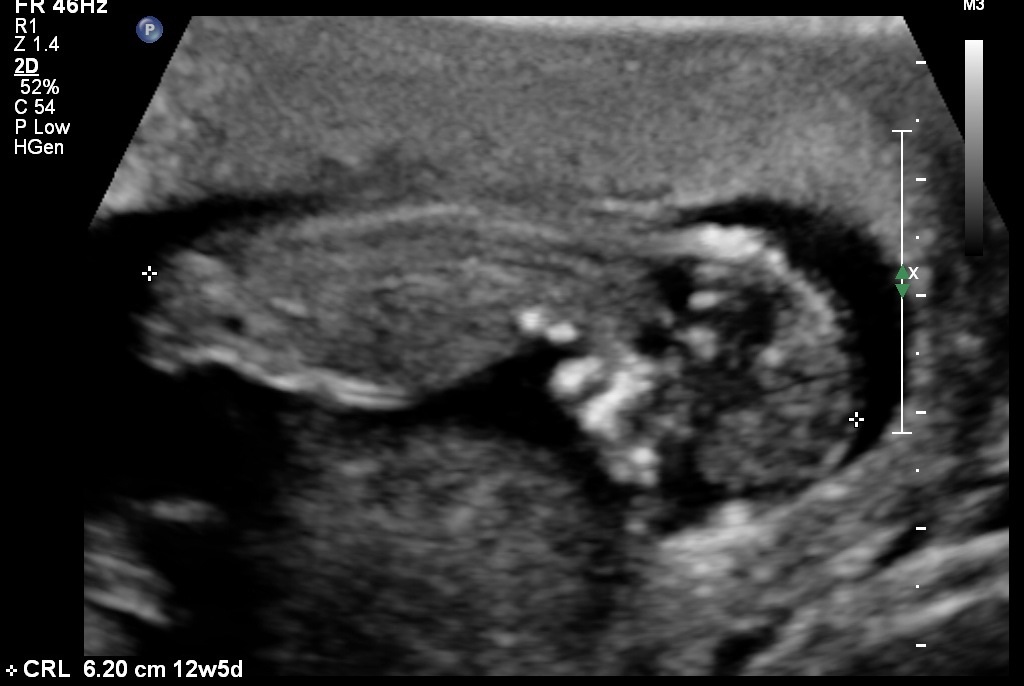

Yeah I wasn't given any good profile shots.:-/ Here's what I have...Attachment 12408Attachment 12409Attachment 12410

Any thoughts? Pretty please?:)

Since I can't see a nub I'd say girl